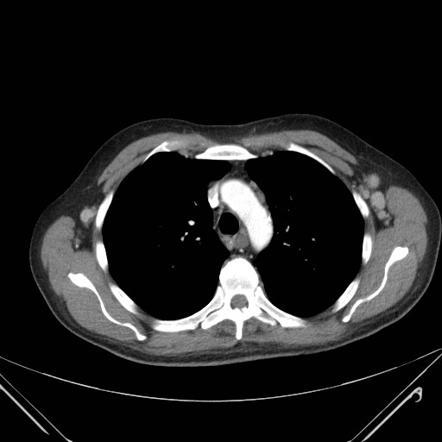

Patient with recurrent epistaxis. Diagnosis?

Multiple (coiled) AVMs in hereditary hemorrhagic telangiectasia (Osler-Weber-Rendu). Telangiectasia, recurrent epistaxis, and multiple-organ AV malformations.

Autosomal-dominant disorder of variable penetrance, chromosomes 9 and 12.